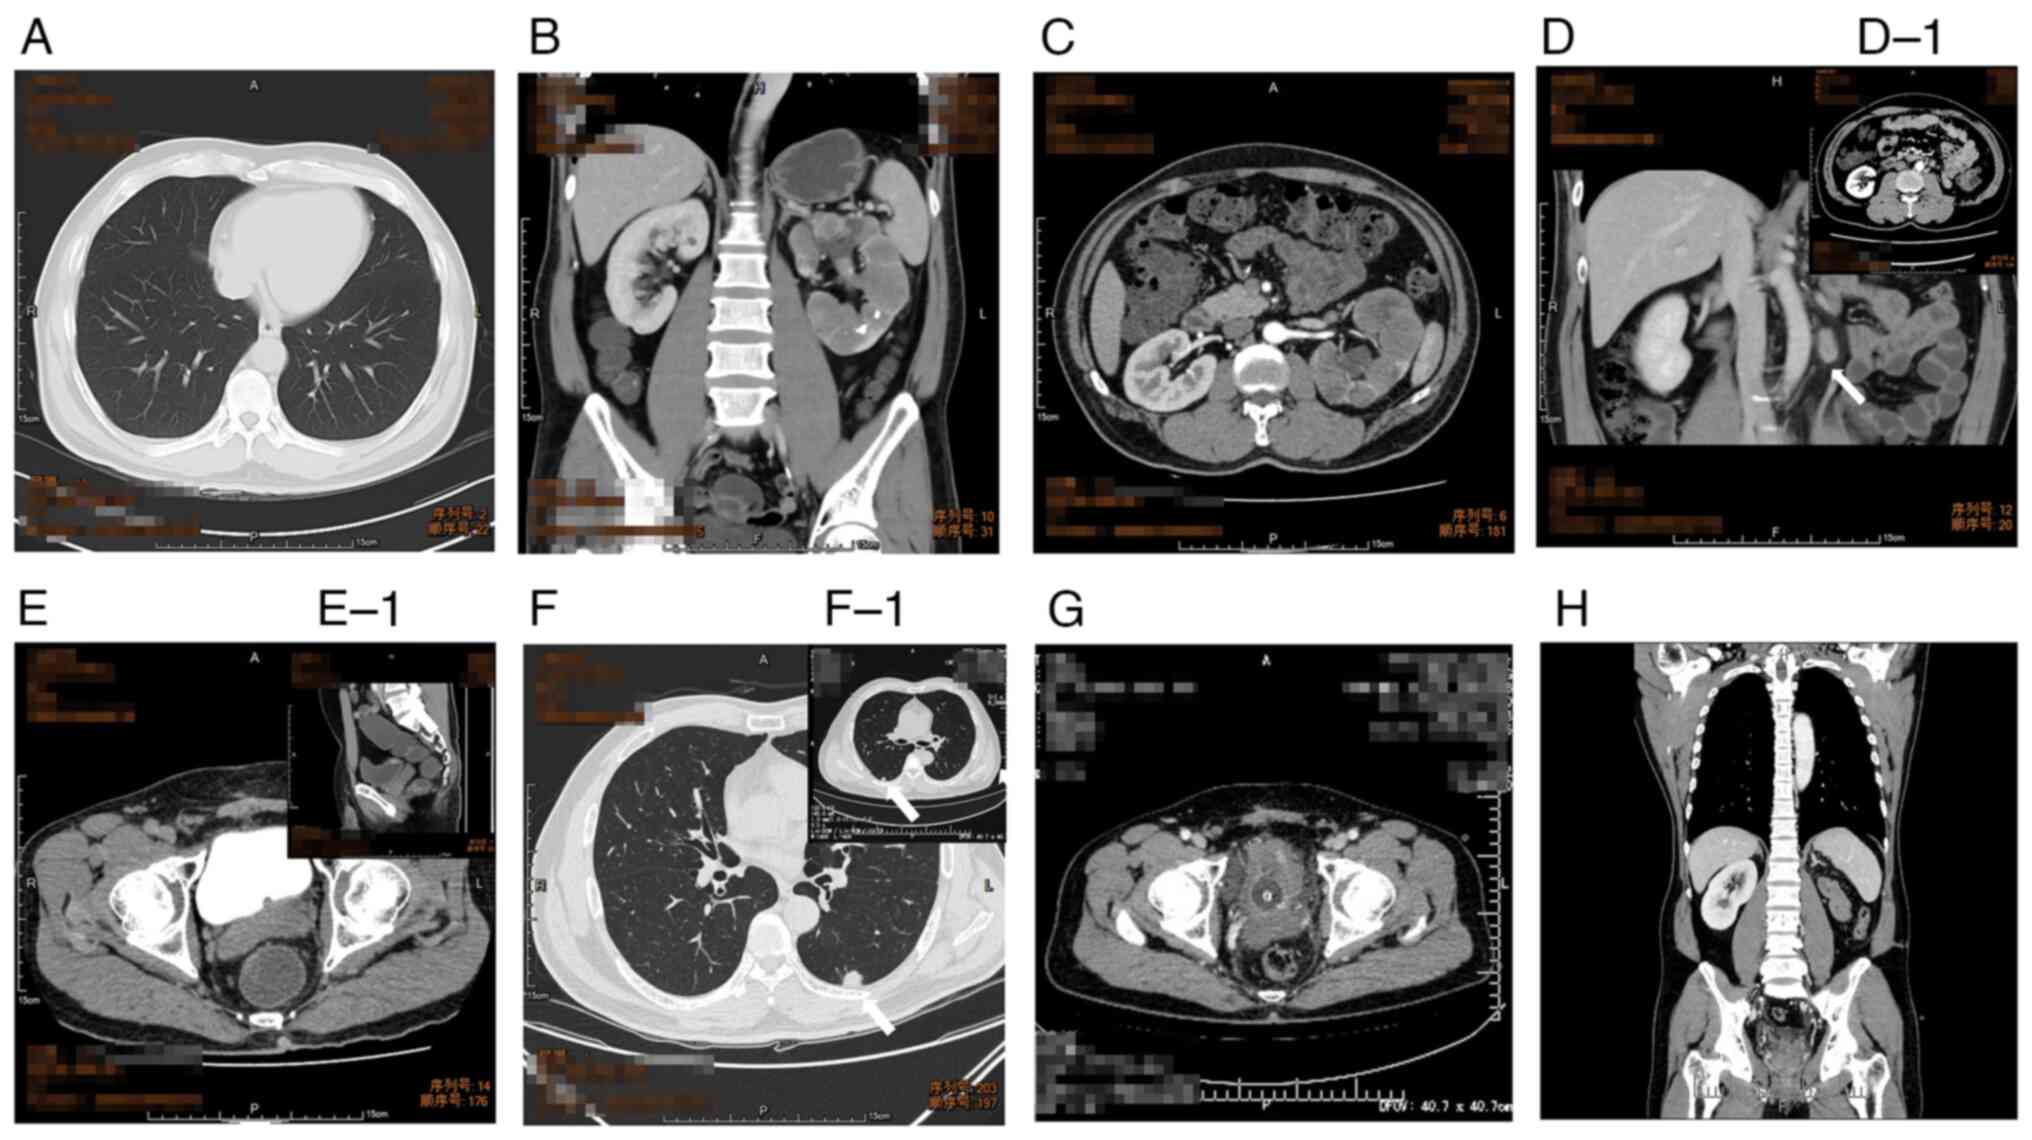

Bladder metastasis from type 2 papillary renal cell carcinoma: A case report

Renal cell carcinoma (RCC) is a common urinary tumor that may be pathologically divided into different subtypes: clear cell RCC, papillary RCC (PRCC) and chromophobe RCC. The most common organs of RCC metastasis are the lung, liver and bones, while bladder metastasis is rare. The treatment for PRCC metastasis is also a problem due to limited clinical data. Therefore, every single case of PRCC metastasis may significantly contribute to establishing a standard treatment protocol. The present study reported on a patient who suffered from repetitive bladder PRCC metastasis with 1.5 years of follow‑up. A 54‑year‑old male patient was diagnosed with left renal pelvic carcinoma in March 2020 and underwent a laparoscopic radical nephroureterectomy of the left kidney. The postoperative histological examination revealed that the tumor was consistent with a type 2 PRCC. Bladder metastasis was discovered three months after the surgery and transurethral resection of the bladder tumor (TURBT) was performed to eliminate the tumor in the bladder. Only three months after the initial TURBT, bladder metastasis was detected again, combined with lung metastasis. The patient refused to undergo radical cystectomy. Therefore, a second TURBT was arranged and targeted drugs were administered. However, both bladder and lung metastases were insensitive to the treatment strategy applied, although immunotherapy was subsequently added. The patient died in October 2021 due to respiratory failure and cachexia. The report aims to provide the whole treatment progress and lessons learned from this case, which is relatively rare.

Figure 1

Figure 2

Figure 3

Figure 4